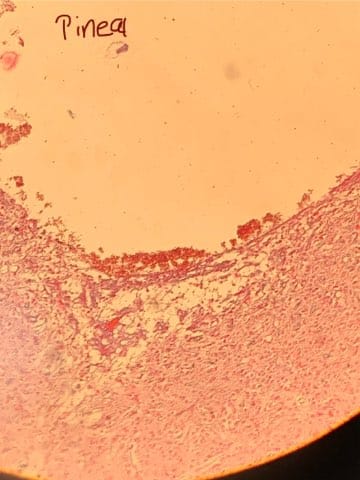

Identify this slide.

Pineal